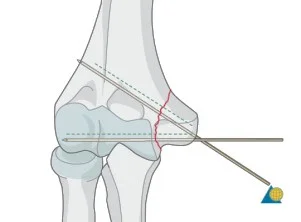

| Screws | Good fixation – stable – Can apply good inter‑fragmentary compression In simple fractures Can be applied percutaneous | ![]() ![]() |